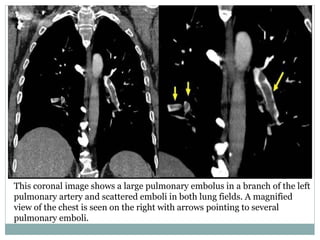

This coronal image shows a large pulmonary embolus in a branch of the left

pulmonary artery and scattered emboli in both lung fields. A magnified

view of the chest is seen on the right with arrows pointing to several

pulmonary emboli.

This coronal imageshows a large pulmonary embolus in a branch of the left pulmonary artery and scattered emboli in both lung fields. A magnified view of the chest is seen on the right with arrows pointing to several pulmonary emboli.